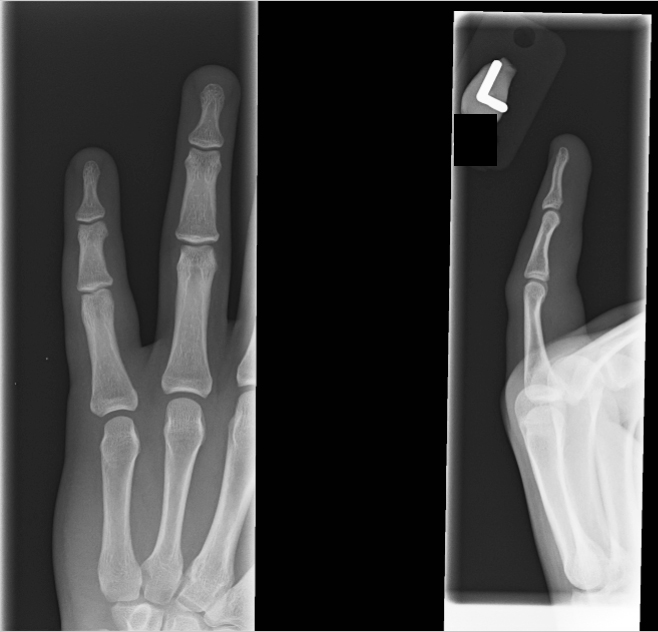

| 15 |

Abnormal fr pp |

Abnormal Right second proximal phalanx base fracture |

Correct |